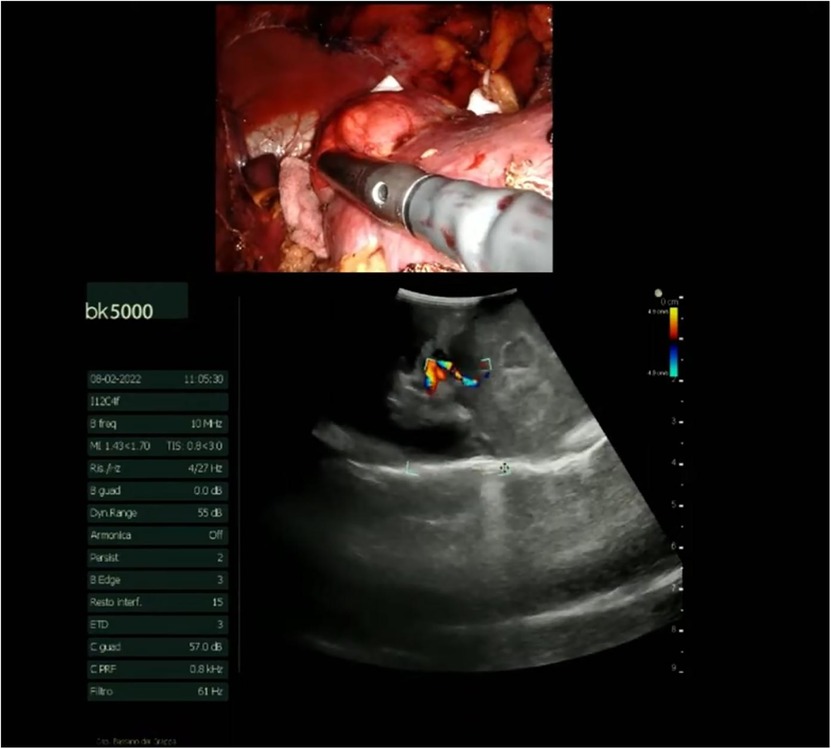

Figure 5

Surgical scene with a close-up of an instrument inside a body cavity at the top. Below, an ultrasound image displays internal anatomy with color Doppler flow, indicating blood movement. The left side shows various ultrasound settings and parameters.

Figure 5. Intraoperative ultrasound.

The procedure begins with an incision of Gerota's fascia, followed by identification of the mass to be removed. The ureter is located, and by following it, the renal hilum is reached. The renal artery is isolated, and a vessel loop is placed in position (Figure 4). Depending on the lesion's characteristics (size, vascularization) and the patient's condition, the renal artery may be clamped or left unclamped. Both approaches are feasible and safe. Intraoperative ultrasound is used to assess the lesion's location, depth within the renal parenchyma, and other characteristics (Figure 5). Indocyanine green is administered intravenously to monitor ischemia (in clamped cases) and vascularization (Figure 6).